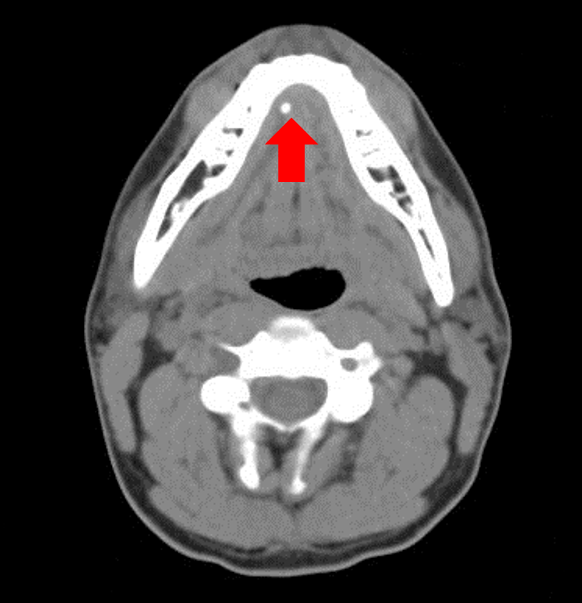

From ostrowonline.usc.edu

Salivary gland stone, Xray Photograph by Science Photo Library Pixels Do Salivary Stones Smell Salivary gland stones are small stones that form in salivary glands in your mouth and can block the flow of saliva (spit). Saliva contains enzymes like amylase which helps break down our food as well as antibacterial agents which. Salivary stones or sialoliths are calcified concrements in the salivary. Salivary stones are small stones that form in the glands of. Do Salivary Stones Smell.